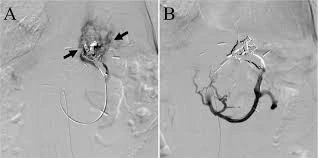

BRTO is a specialized procedure used to treat gastric varices, which are enlarged veins in the stomach caused by portal hypertension.

A catheter with a balloon is inserted into a vein and positioned near the abnormal veins. The balloon temporarily blocks the vein while a special medication is injected to close the varices.

Variceal embolization is a procedure used to treat varices, which are enlarged veins that develop due to high pressure in the portal vein. These veins can rupture and cause life-threatening bleeding.

During the procedure, a catheter is inserted into the affected vein and embolic materials are used to block the abnormal blood vessels.